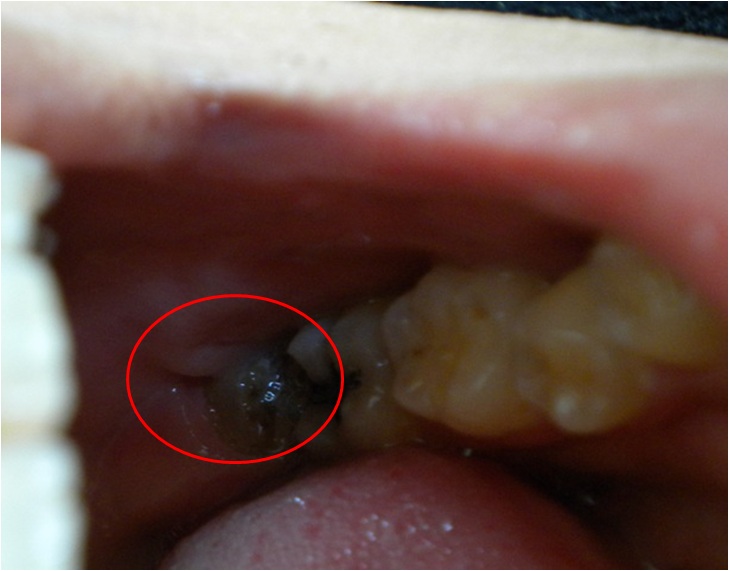

Bdfore After 抜いた歯

分かりにくいが、親知らず 親知らずがなくなって、 骨もいっしょに

がうっすら見える。 歯ぐきだけに。 ついてきた・・・。